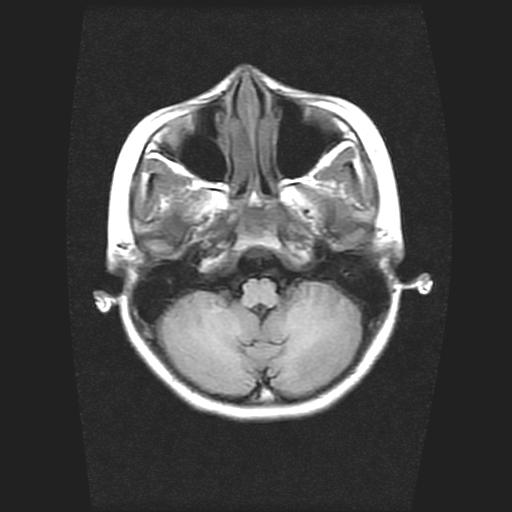

标题: PED0378:女孩9岁,癫痫,看能否停药 [打印本页]

标题: PED0378:女孩9岁,癫痫,看能否停药

9岁女孩,三岁时诊断为癫痫,一直服丙戊酸钠,现患者一般情况良好,家长复查核磁片,看能否停药..

巨脑回